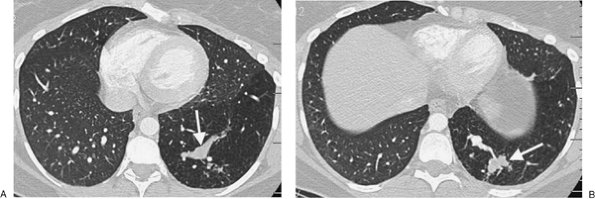

FIGURE 16-2. Intralobar sequestration. A: CT of a 37-year-old woman with chest pain shows a prominent tubular structure in the left lower lobe (arrow). The surrounding lung, also part of the sequestration, is hyperlucent. B: CT at a more inferior level shows the tubular structure leading to a lobulated mass (arrow) in the left lower lobe. C: CT with mediastinal windowing shows the tubular structure be a vessel (arrow). D: CT of the upper abdomen shows a prominent vessel (arrow) arising from the abdominal aorta and heading toward the left lower lobe. E: Coronal reformatted CT confirms that a vessel arises from the abdominal aorta (arrow) and heads superiorly toward the left lower lobe. F: Paddlewheel reformatted CT shows drainage from the left lower lobe mass to the left inferior pulmonary vein (arrow).

P.266